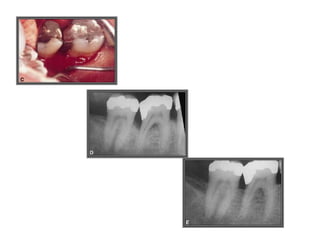

TRATAMENTO DAS LESÕES

ENDOPERIODONTAIS

Hemisseccção

DEL RIO, 1996